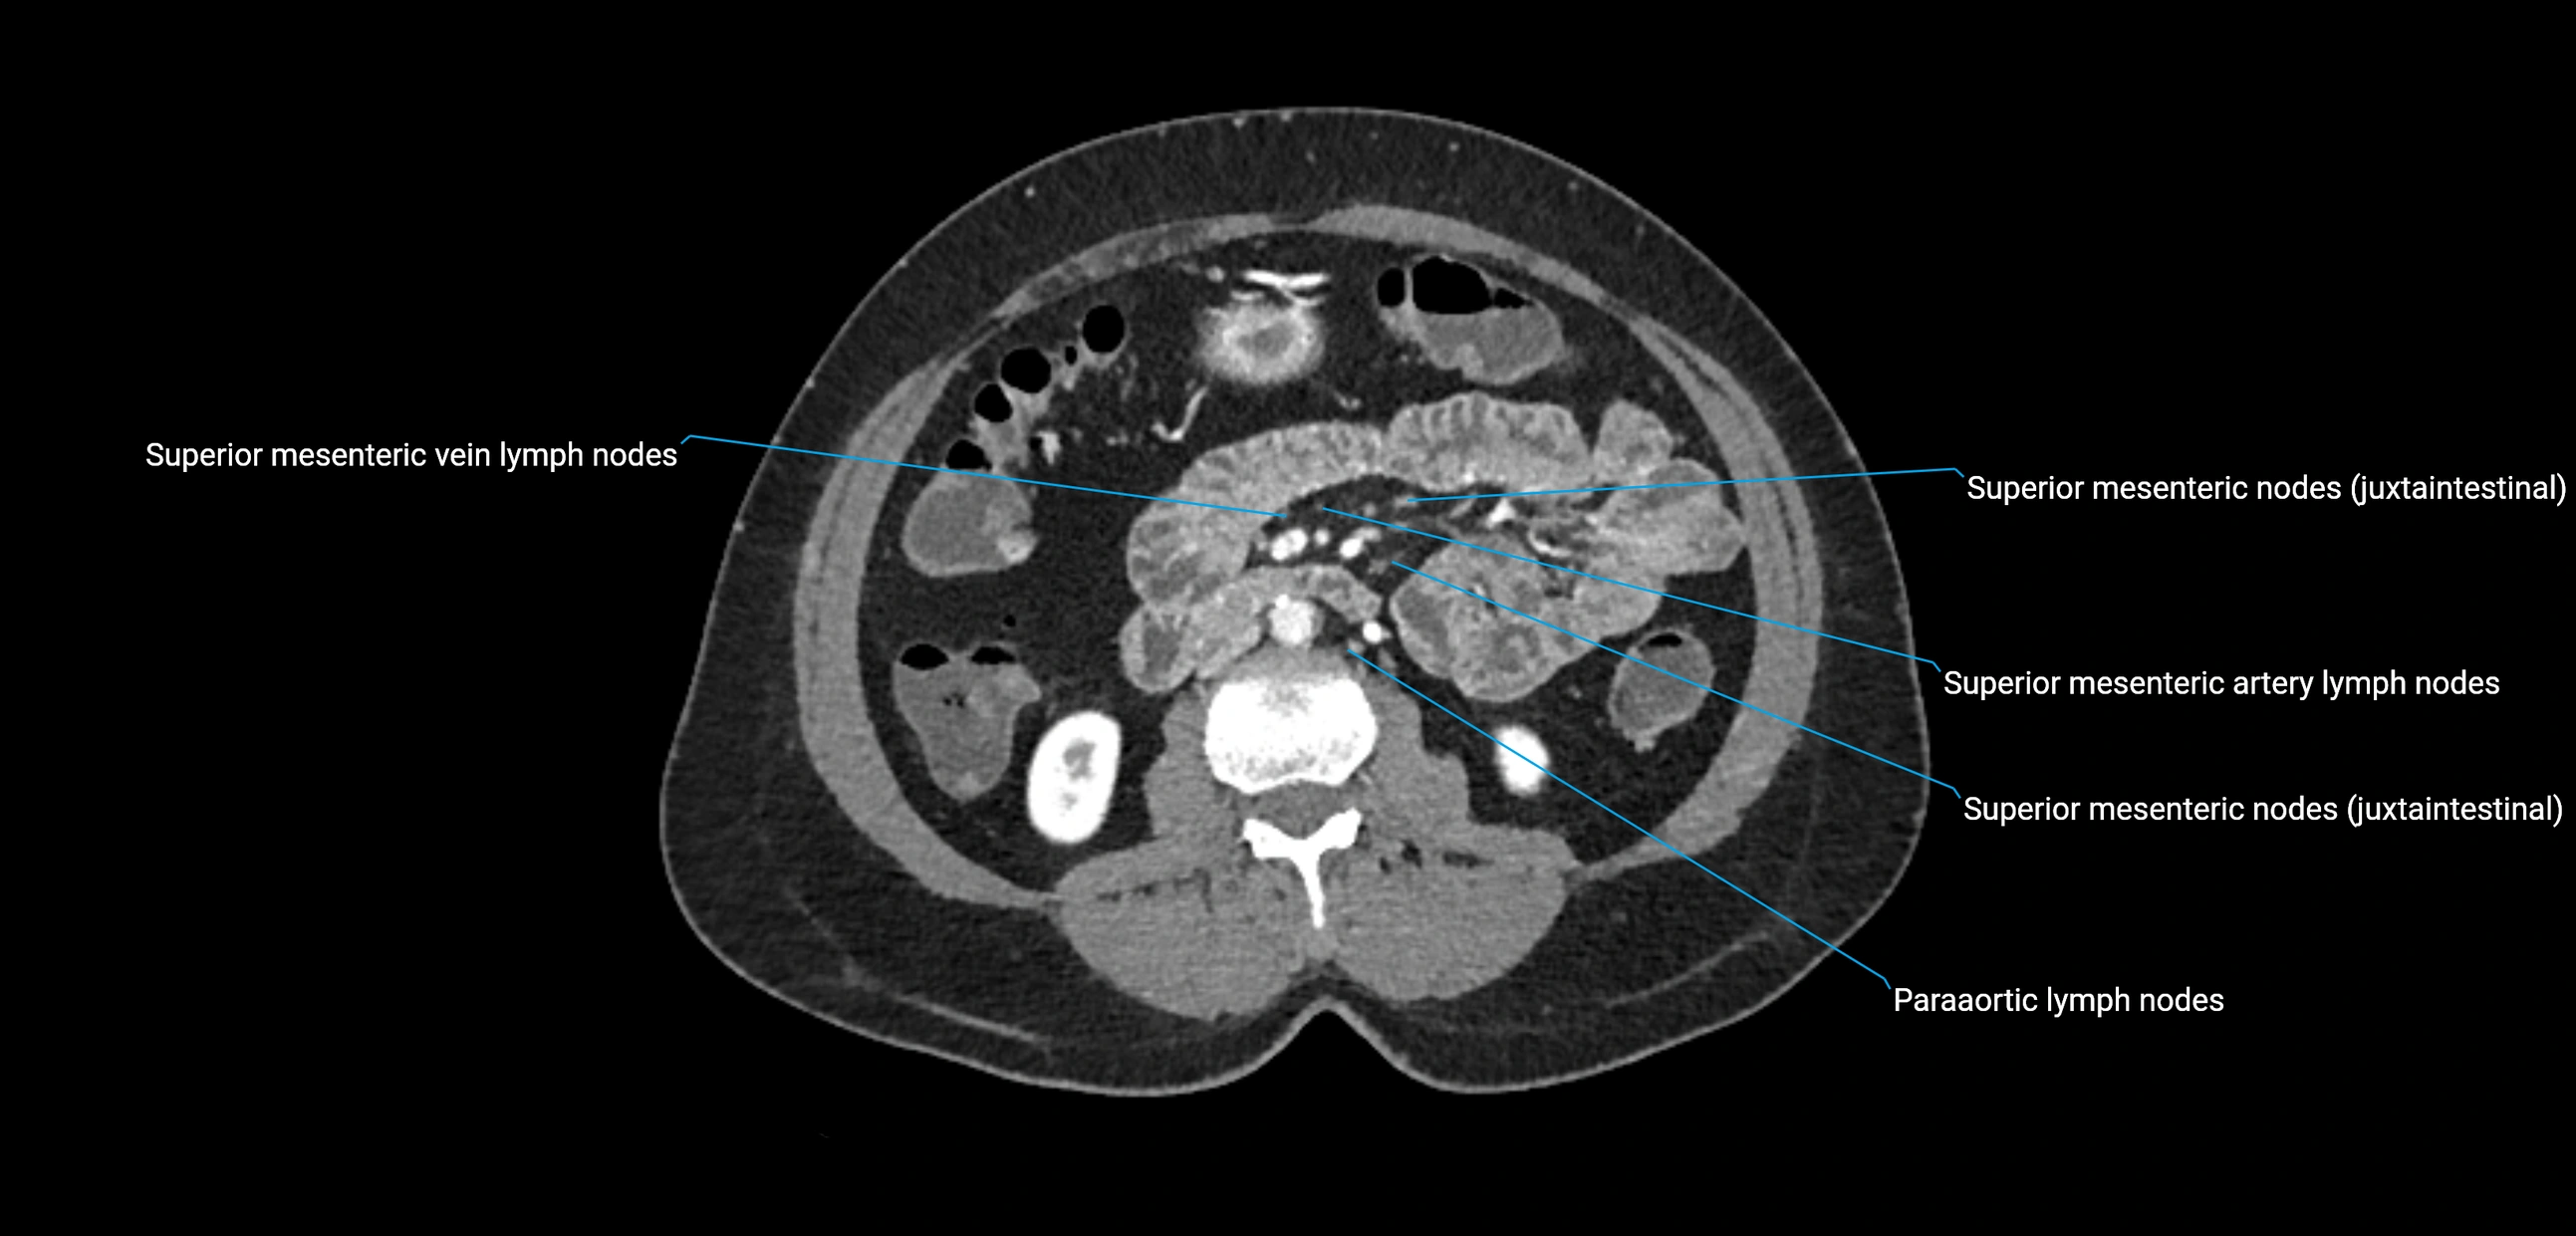

CT Appearance

CT Pre-Contrast:

• Nodes appear as soft-tissue density nodules adjacent to the aorta and IVC

• Calcification may be seen in chronic infections (e.g., tuberculosis)

CT Post-Contrast:

• Normal nodes enhance homogeneously

• Malignant nodes may show heterogeneous enhancement, central necrosis, or conglomerate formation

• Size >1 cm short axis is suspicious, though morphology and distribution are equally important